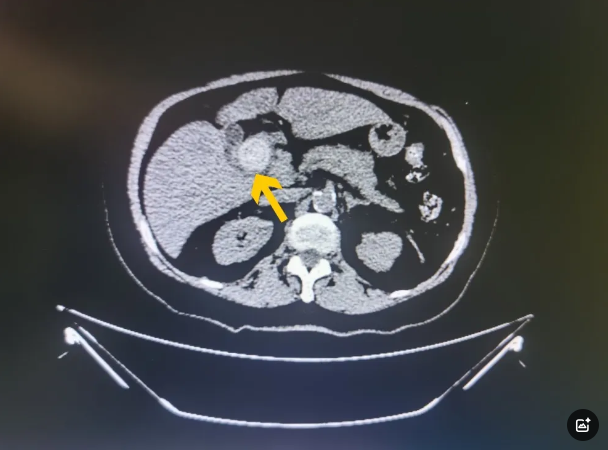

在医学的舞台上,每一次成功的手术都是一场与病魔的精彩博弈。今天,让我们走进这样一个故事,看看在微创时代,面对复杂的膈疝,医生们如何“化繁...